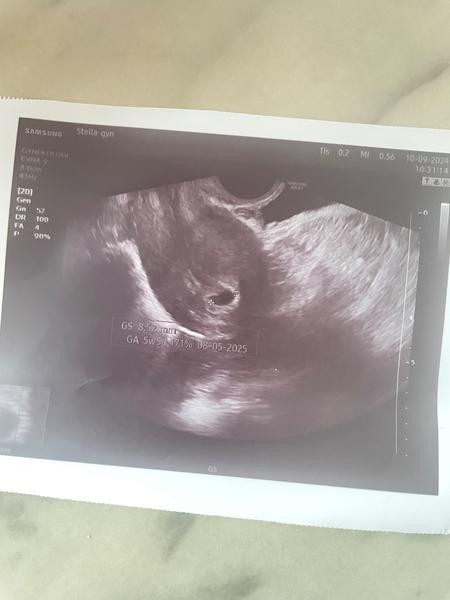

@vlasta1981 holky tak dnes jsem byla na gyndě. Jsem prý 5+5 a neni tam jeste embryo. Ze bud se tam udela nebo ne ☹ co si otom myslite? Posledni ms 29.7.2024 ovulace byla 17den cyklu. V deloze to pry je. Ale zarazilo me, ze pry na hcg vubec nezalezi. Ze dulezity je utz. Co myslite je jeste sance?

podľa mňa šanca stále je, držím palce 🙏 no v podstate áno, je to tak že ak vezmeme do úvahy utz a hcg, tak utz je presnejší ukazovateľ. Občas sa bohužiaľ stáva že ostane len prázdny gestačný vačok 😕nebolo tam vidieť zatiaľ ani žltkovy vak? kedy máš ďalšiu kontrolu alebo aký je teraz postup?

@katezina11 dalsi kontrolu mam v utery 17.9. tak uvidime. Je to bud a nebo.

Nic jineho mi nerekla.